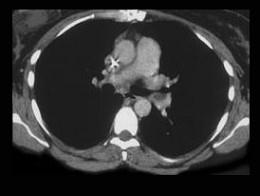

问题 女,51岁,心脏手术后,突感胸痛,结合CT图像,最可能的诊断是 ( )

选项 A、肺癌 B、肺不张 C、支气管扩张 D、肺水肿 E、肺栓塞

答案 E